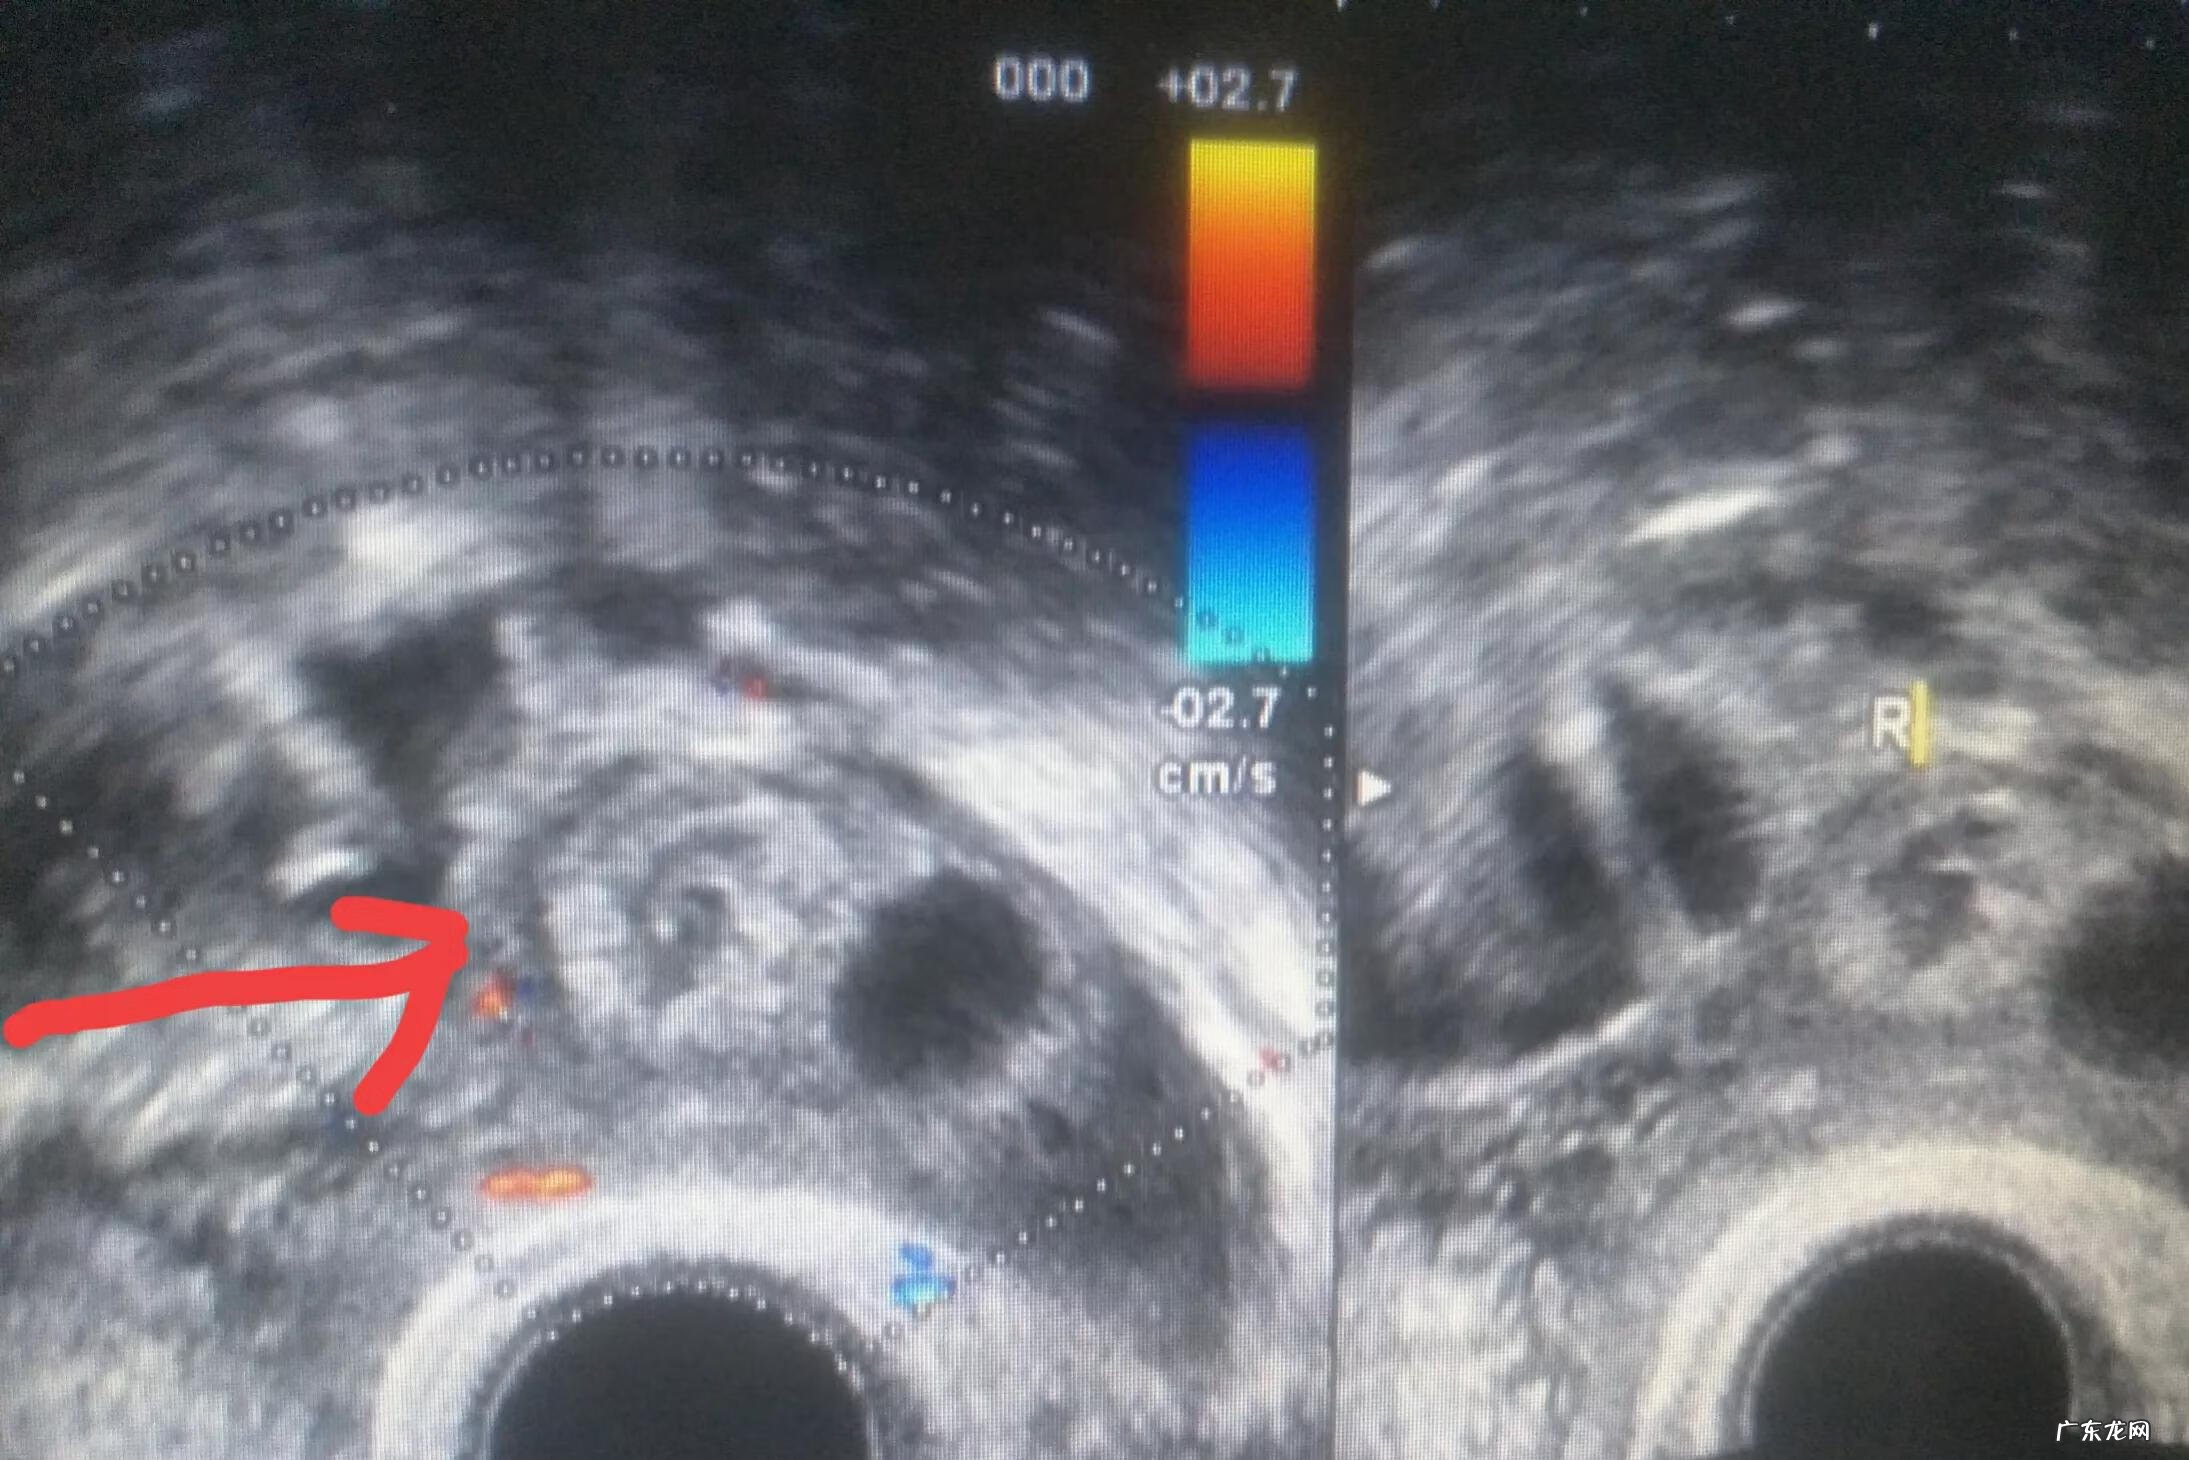

【怀孕42天孕囊还在卵巢 卵巢妊娠手术后还能正常怀孕吗】右侧附件区混合性包块(妊娠物)